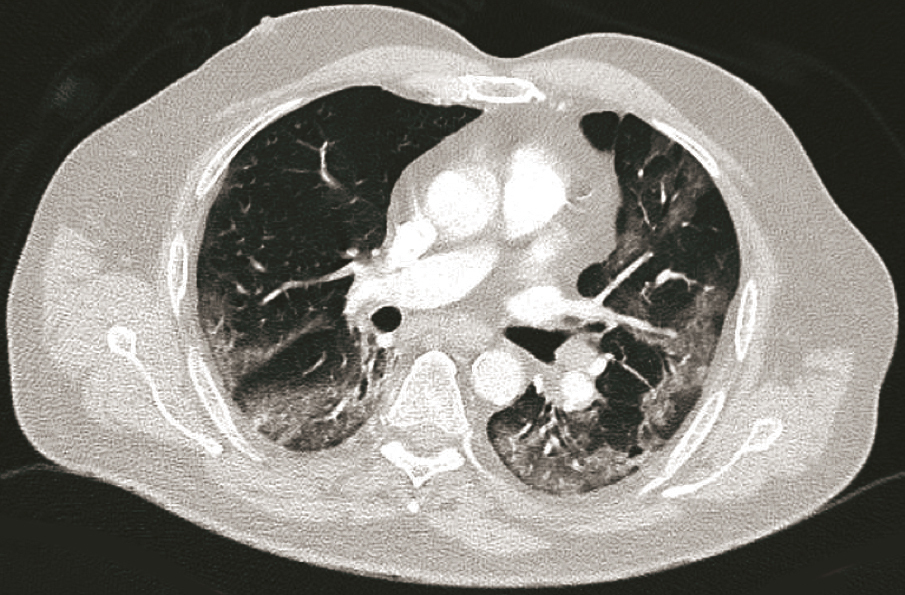

Homme de 67 ans, diabétique, consultant pour une dyspnée avec fièvre. Quel est votre diagnostic ? Pneumopathie à mycoplasme Légionellose Pneumonie organisée Pneumopathie Covid-19 Pneumopathie à l’amiodarone OK Valider mes réponses